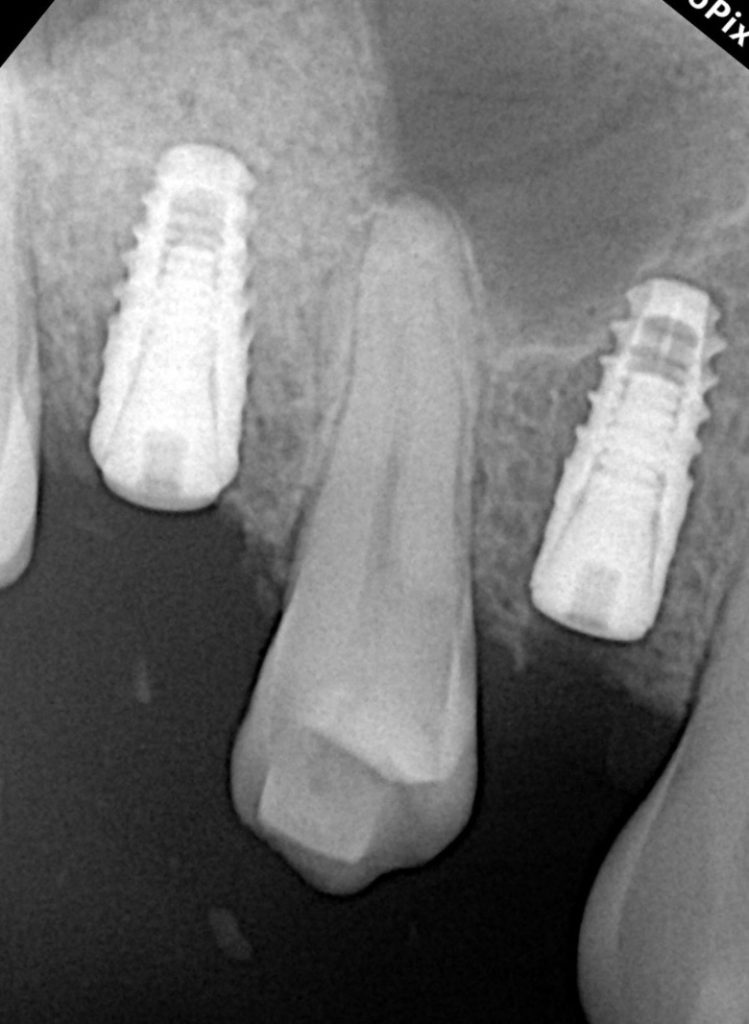

The patient presented with a missing maxillary first molar and reduced residual ridge height of approximately 6 mm (Fig 1). A CBCT scan revealed adequate bucco-palatal width and sinus floor proximity, indicating the need for a crestal (indirect) sinus lift rather than a lateral window procedure.

A Swiss-made tapered implant (4.1 × 10 mm) was inserted into the prepared osteotomy with 40 Ncm torque (Fig 4). The implant apex extended slightly into the augmented sinus cavity, achieving excellent primary stability and favorable bone compression.

After confirmed osseointegration, a screw-retained crown was fabricated and torqued to 25 Ncm. The occlusion was adjusted for light centric contacts and canine guidance (Fig 5). Follow-up at 6 months revealed healthy peri-implant tissue and radiographically stable crestal bone (Fig 6).